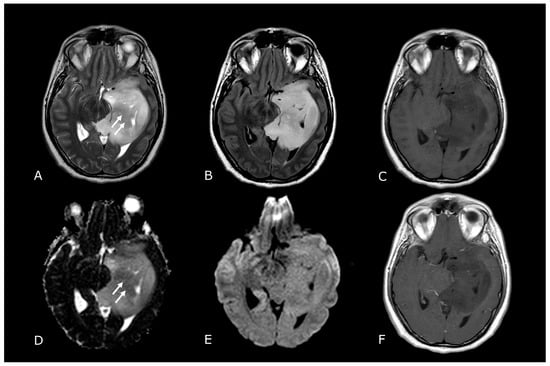

4. Diffusion Weighted and Diffusion Tensor Imaging

4.1. DWI in Brain Tumors: Technical Notes, Clinical Application and Prognosis

2. Conventional/Morphological MRI